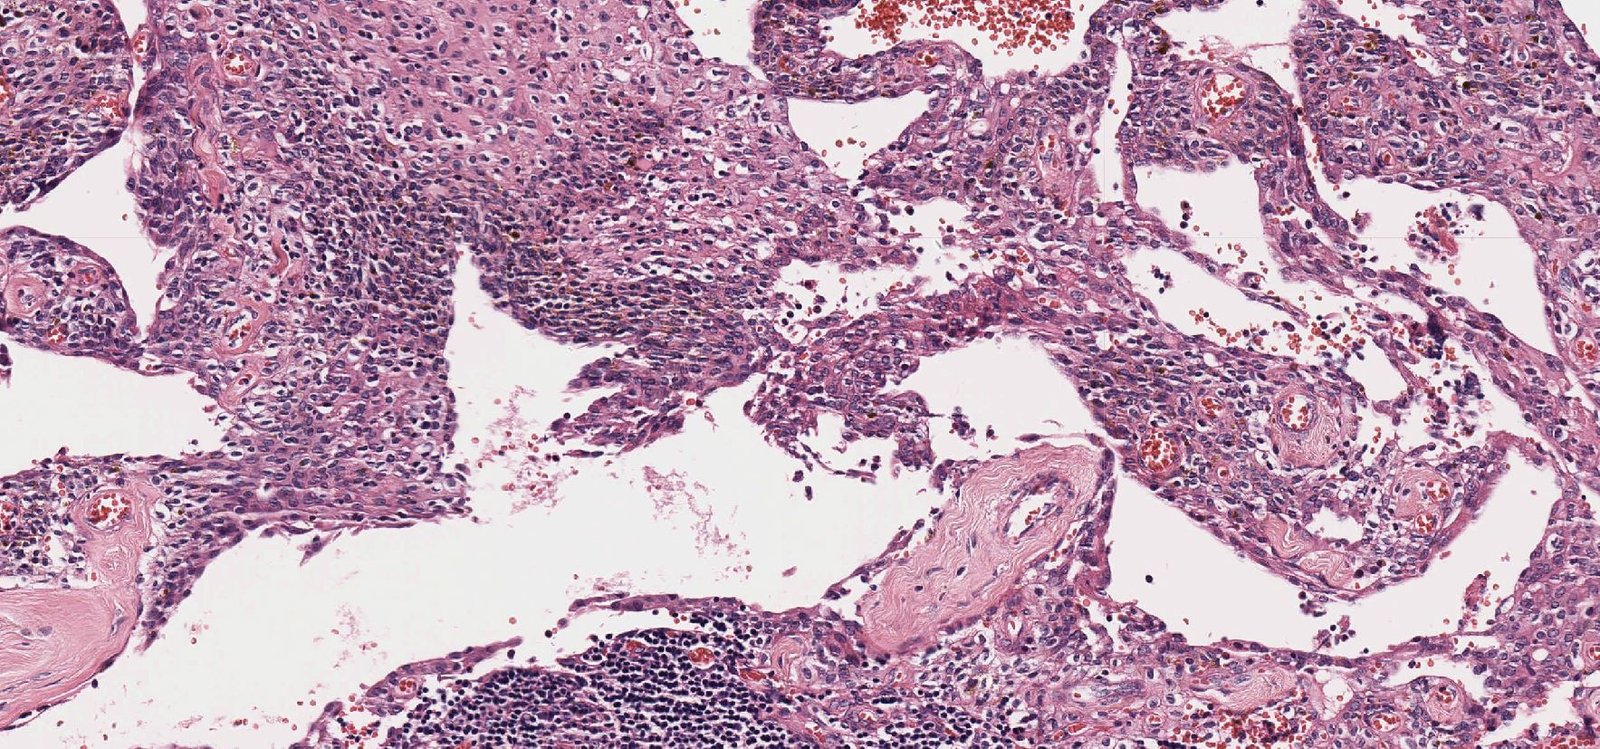

Case: NeckMass

Final Diagnosis: